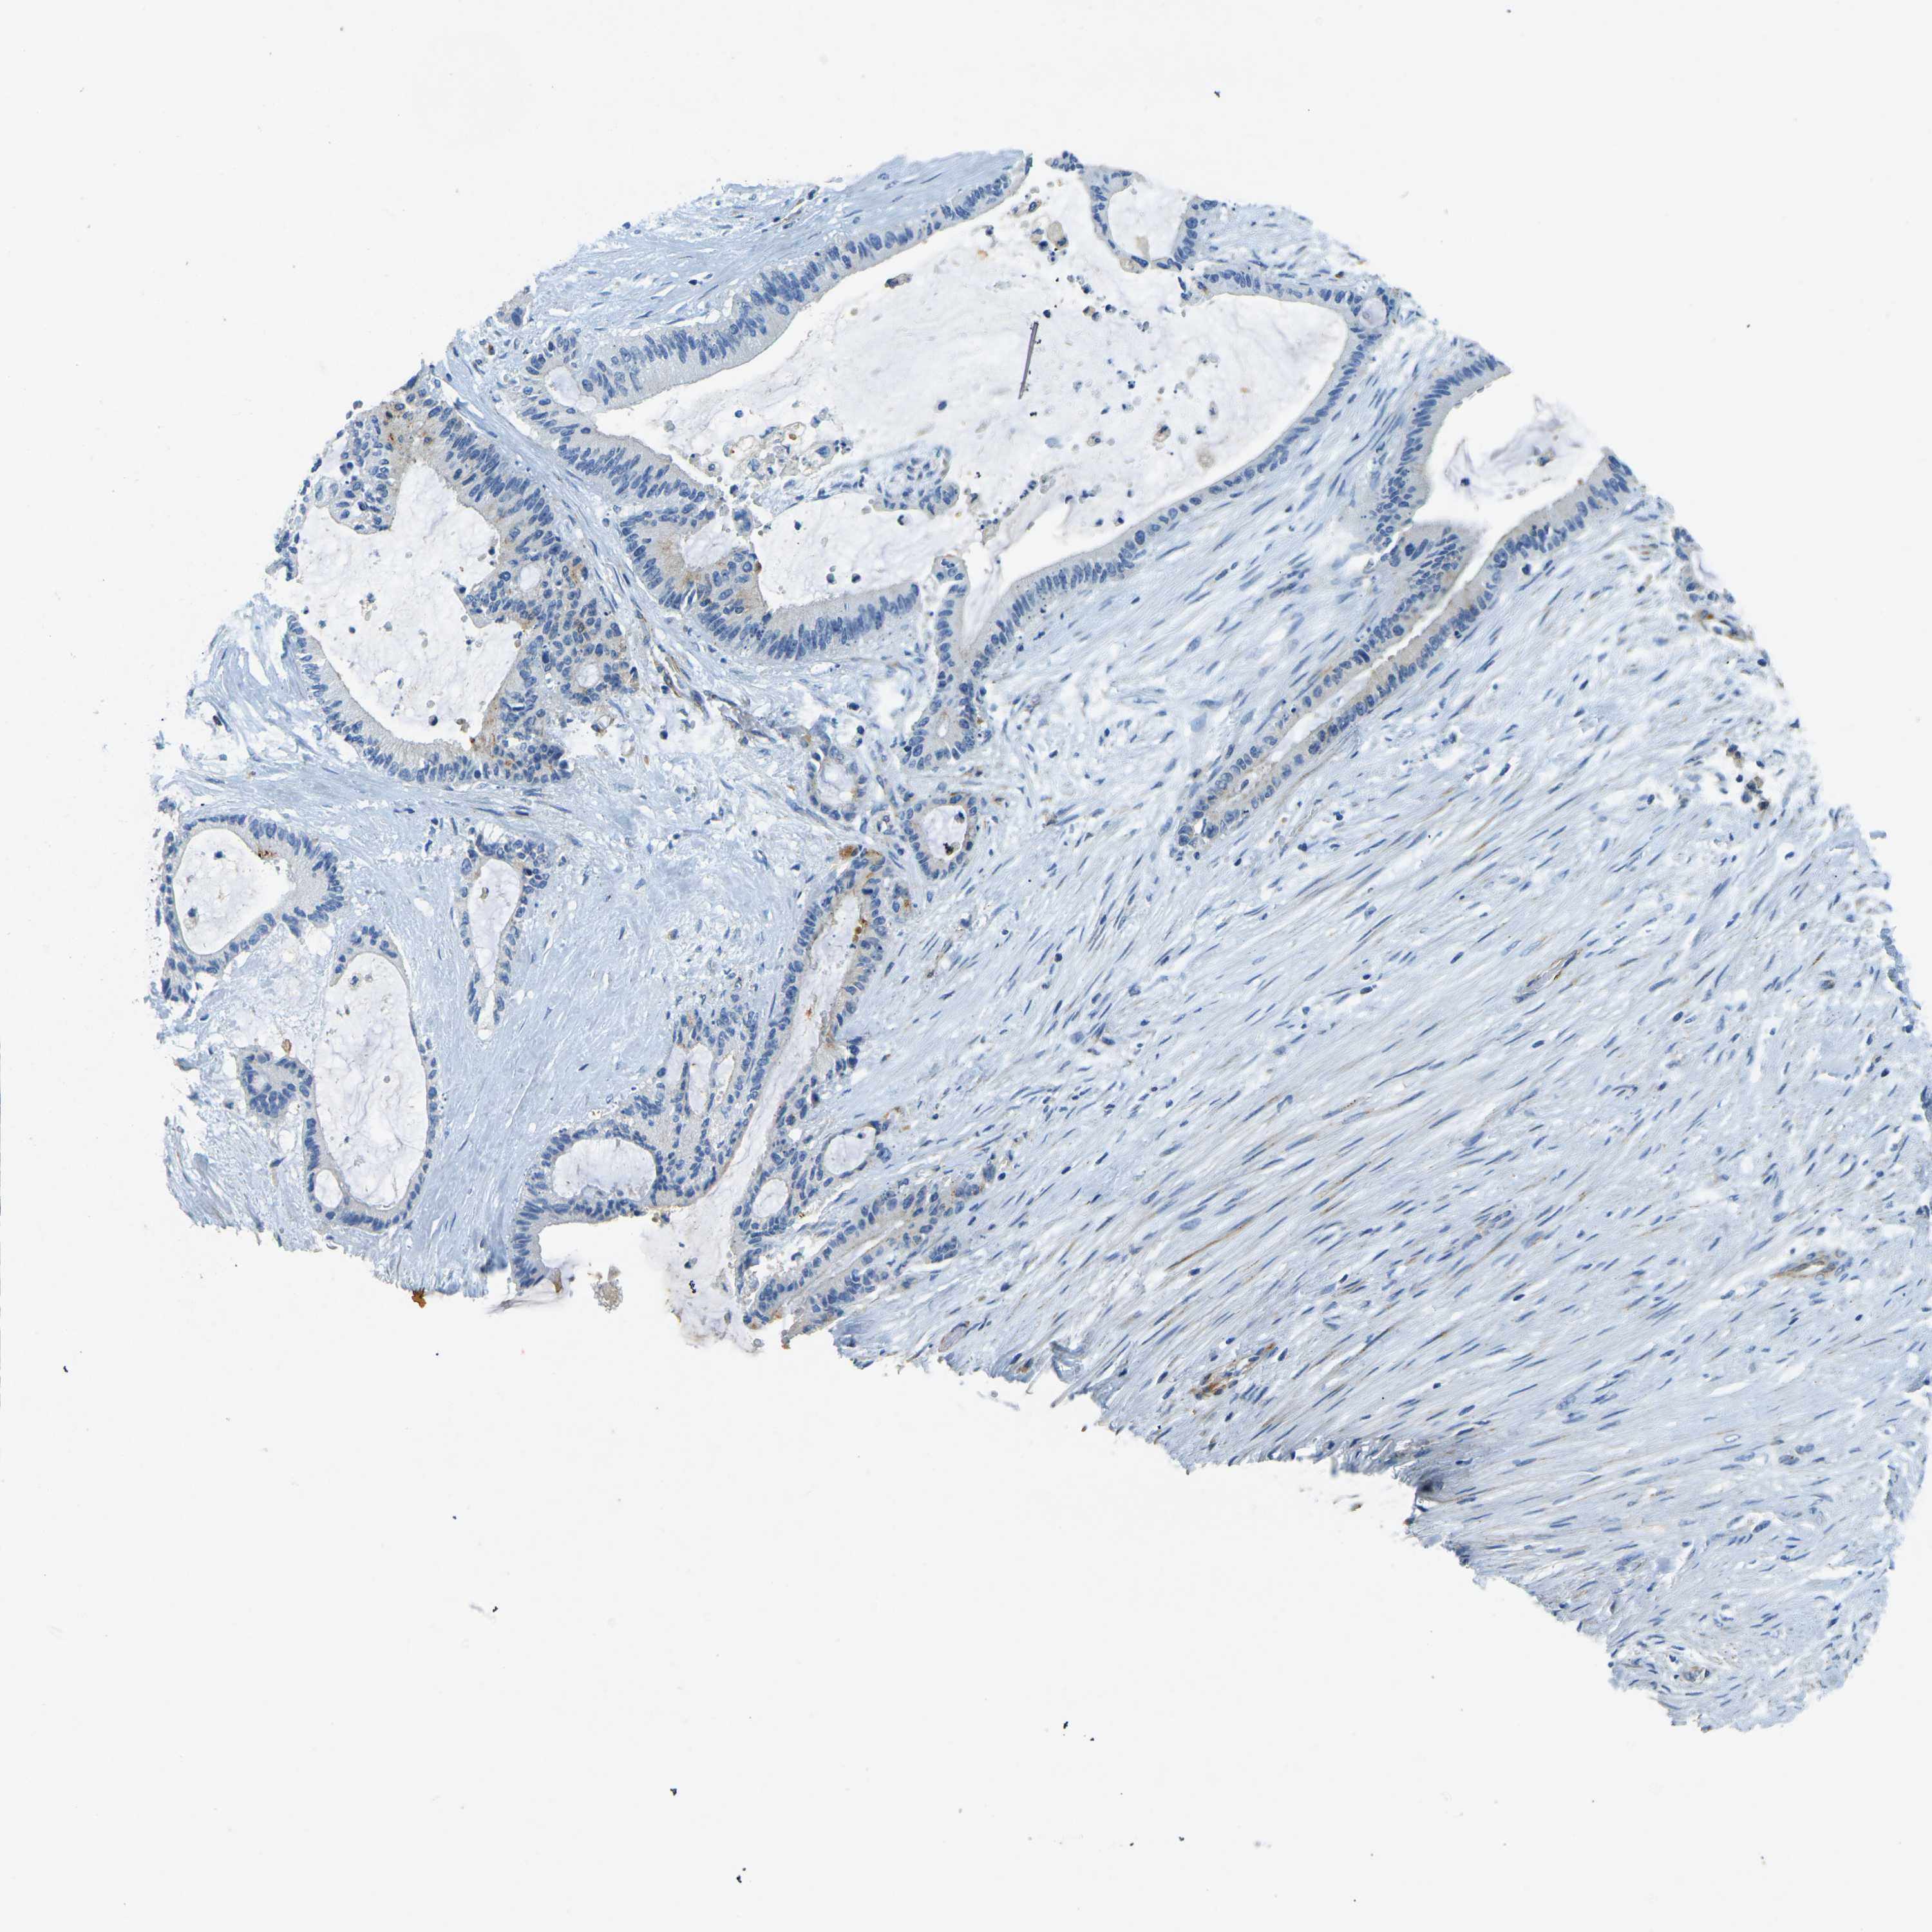

LIVER CANCER - Protein expressioni

A mouse-over function shows sample information and annotation data. Click on an image to view it in a full screen mode. Samples can be filtered based on level of antibody staining by selecting one or several of the following categories: high, medium, low and not detected. The assay and annotation is described here.

Note that samples used for immunohistochemistry by the Human Protein Atlas do not correspond to samples in the TCGA dataset.

Antibody stainingi

Antibody staining in the annotated cell types in the current human tissue is reported as not detected, low, medium, or high, based on conventional immunohistochemistry profiling in selected tissues. This score is based on the combination of the staining intensity and fraction of stained cells.

Each image is clickable and will lead to virtual microscopy that enables deeper exploration of all samples and also displays staining intensity scores, fraction scores and subcellular localization as well as patient and tissue information for each sample.

Antibody HPA006889

Antibody CAB011498

Staining

High

Medium

Low

Not detected

Intensity

Strong

Moderate

Weak

Negative

Quantity

>75%

75%-25%

<25%

None

Location

Nuclear

Cytoplasmic/membranous

Cytoplasmic/membranous,nuclear

Cholangiocarcinoma

Carcinoma, Hepatocellular, NOS